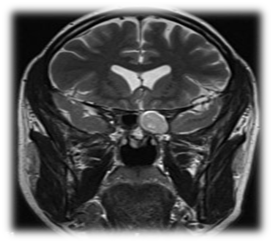

The commonest pathogens include Staphylococcus aureus, aerobic Gram-negative bacilli and anaerobes.10-14 These patients presented with headache, rhinorrhea, nasal obstruction, and blurred vision. The most common presenting symptom of sphenoid sinus disease is mainly headache. In the majority of previous reports, headache was nonspesific in location, quality and intensity.15 Physical examination and endoscopic finding may show mucopurulent secretion at the sphenoethmoidal area, edema of the sphenoethmoidal recess mucosa and polypoid tissue in the sphenoethmoidal recess. In CT scan of the sinuses (Figure 1) will show opacification in the sphenoid sinus, with mucosal wall thickening and air-fluid level. Management of these patients is medical treatment with antibiotic based on culture with topical corticosteroid and decongestant, the surgical intervention (endoscopic sphenoidotomy) (Figure 2) if failed medical treatment or patient presented with complications.

Figure 1 CT scans sinuses with homogenous opacification of both sphenoid sinuses.